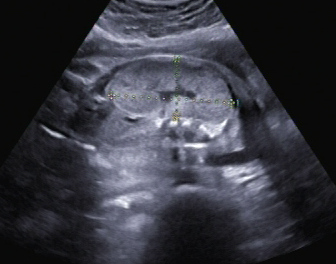

Ein zunächst durchgeführtes CTG war unauffällig. Im Rahmen der sonografischen Untersuchung zeigte sich der Fötus soweit beurteilbar zeitgerecht entwickelt. Dennoch konnte ein Anhydramnion festgestellt werden(Abb. 1, 2), weshalb auch kein fetales Gesicht darstellbar war (Abb. 3).